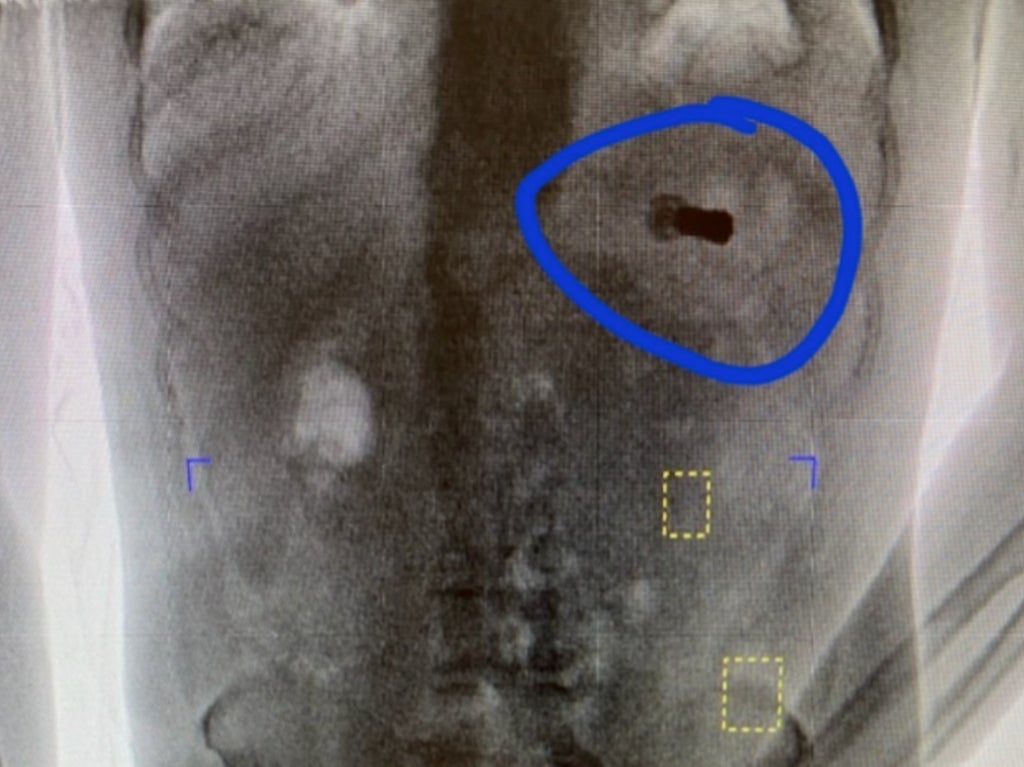

An Alabama prisoner was found to have swallowed a shotgun shell after a prison body scanner picked-up the item sitting in his stomach.

The sheriff’s office said in a Facebook post that the man had been arrested elsewhere in the county, and that the shotgun shell in his stomach was found when he walked through a body scanner to be checked-in to the facility.

He was seen by medics and an image of the shell sitting in the prisoner’s stomach was shared to Facebook, much to the astonishment of the officers.

The shell was allegedly from a 410-gauge shotgun, although it was not clear when the shell was swollen, and why.